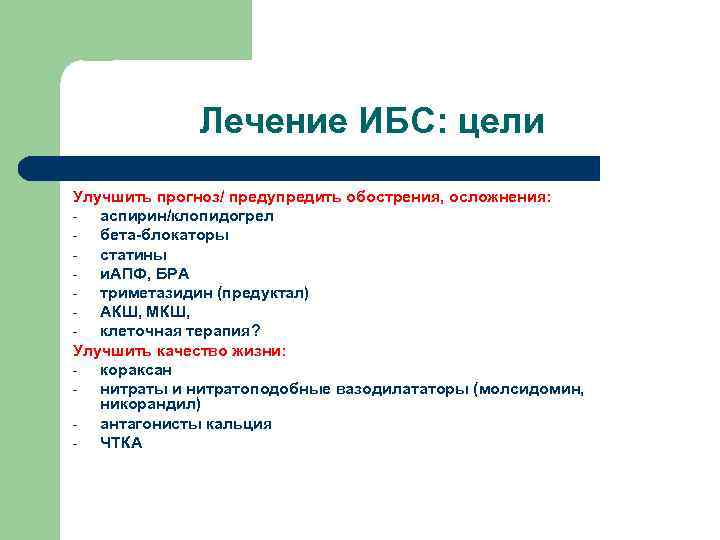

Лечение ИБС: цели Улучшить прогноз/ предупредить обострения, осложнения: аспирин/клопидогрел бета-блокаторы статины и. АПФ, БРА триметазидин (предуктал) АКШ, МКШ, клеточная терапия? Улучшить качество жизни: кораксан нитраты и нитратоподобные вазодилататоры (молсидомин, никорандил) антагонисты кальция ЧТКА